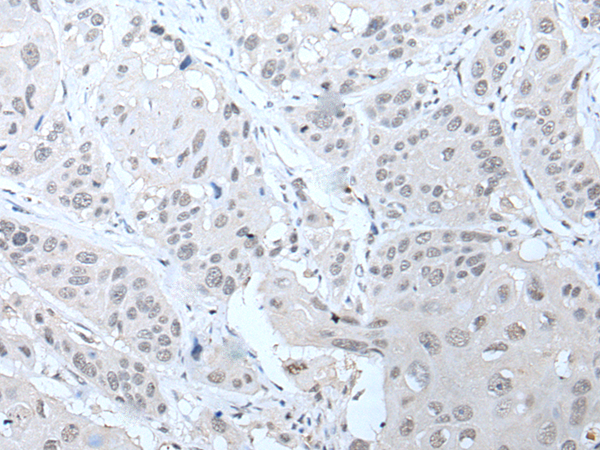

IHC positive control: |

Human thyroid cancer and human liver cancer |